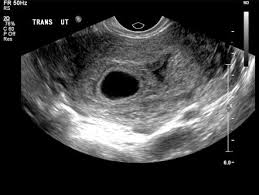

Gestational Sac In Pregnancy And Meaning If Empty

Gestational Sac In Pregnancy And Meaning If Empty from www.verywellfamily.com

The number of fetuses and gestation sacs. Dating scans also reveal other important information such as: Learn english languages from a voice translator. Since chromosomal abnormalities can result in impaired cardiovascular. Scanner translation and definition in tamil, related phrase, antonyms, synonyms, examples for scanner Will ultrasound scan affect baby during pregnancy check the doctor opinion tamil news from samayam tamil, til network. A dating scan is an ultrasound examination which is performed in order to establish the gestational age of the pregnancy. The size of the fetus, from which the gestational age is estimated.